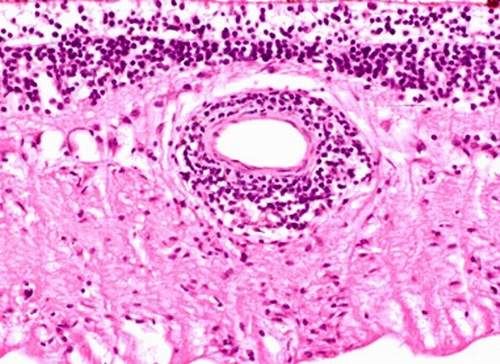

Tiêu bản tổn thương loét miệng áp-tơ.